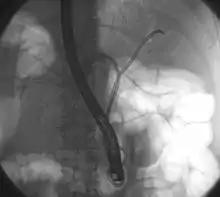

Klatskin tumor during ERCP. Wires were inserted into the left and right biliary systems. Both parts were injected through a tube with contrast, but there is no contrast visible in the area of confluence of the two systems | |